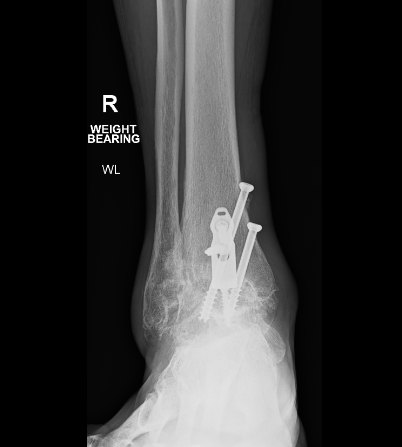

This one felt like a couple of cold needles pressed into flesh above ankle on left. If I have any more issues with this ankle then I am screwed. Actually as it turns out, I am unscrewing. If we review the tape from 18 months ago and 18 hrs ago I think we see the problem.

I am no Orthopod but doubt that is supposed to happen especially if associated with vague pain. Contacted surgeon but he was at a Meccano Retrospective in Birdsville for the weekend. So, physician heal thyself. What I found is that after 3 hours mowing on Sidewinder the ankle is so swollen that you no longer see the screws. Yay. Sadly around midnight the swelling has decreased and the feeling of someone dripping cold water on your ankle returns. Of course could also indicate another pee stop is needed after 5 hrs sleep. Lets move further north as the Bishop said to the Actress. We can probably safely assume that the left shoulder is as good as its going to get so lets file this away in the “definitely not good news” folder. Its not debilitating as such but certainly limited movement for certain exercises like military presses etc. If the right shoulder is the benchmark (for doing benchpresses) and we give it a 9.5/10 score then the left shoulder comes in at 7.1 I guess. (gave it an extra 0.1 cause its way cool having matching scars). Which reminds me, the tatt hasnt washed off yet. Yay. The real issue with these continuing medical situations (apart from cost!) is it makes it virtually impossible to get into any routine of gym, golf, walking, ice skating….One thing I know about me is that I need physical activity to keep the kgs at bay. Simply eating better doesnt do it if sit around all day. And before you say it I hate bike riding whether moving or stationary. There was that one time 10 years ago when it felt really great until after 10 minutes realised the seat had fallen off at the start. On a side note never understand people who go to the gym just to use walking treadmills. Duh?